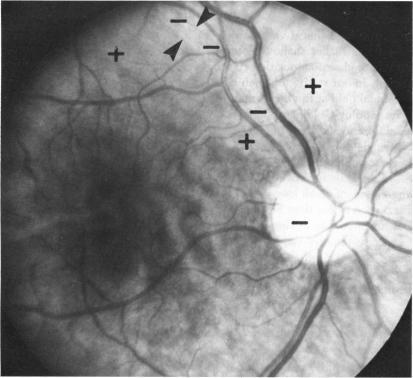

The following is a brief summary of the results in our ten groups of cases. The positive features of laser scotometry are emphasized. The normal response is well defined: there are no uncertain blind spot margins. The peripheral field is probably extended beyond 60 degrees nasally and superiorly. The size and shape of the small central scotomas associated with macular holes are easily defined and correlated directly with the visible edge of the hole. This result is distinct from the intact subjective response with cystoid maculopathy and surface wrinkling retinopathy. Plotting the margins of peripheral abnormalities such as retinal detachments, retinoschisis, and lattice degeneration is easily done. Schisis is distinguished by an absolute scotoma. This scotometry is facilitated by a larger "normal" field with the laser instrument. Lattice degeneration causes a field defect. A branch retinal artery occlusion shows a slightly jagged border, difficult to detect by standard methods. A cotton-wool spot does not show a total nerve-fiber-bundle defect. Small absolute scotomas are correlated with degenerative changes within nevi. Degenerative changes over small melanomas--ie, the orange spots--also produce absolute field defects. "Bear track" lesions have a normal field, whereas dense black isolated lesions are associated with absolute scotomas. In macular degeneration the bright laser test object is usually visible to the patient within detachments of neuroepithelium, detachments of the pigment epithelium, and over recent subretinal neovascularization. Response is absent over sharply-defined zones of pigment atrophy and over late subretinal fibrovascular mounds. In contrast to the degenerative cases, a selection of hereditary cases showed no direct correlation between the zone of pigment atrophy and the zone of absolute scotoma. The scotoma was much larger than the atrophic region, extending to the edge of the cream-colored subretinal spots. The laser target method sharply defines the absolute scotoma associated with papilledema. It also detects a slit-like nerve-fiber-bundle defect, suggesting progressive damage. Small, but possibly not the earliest, scotomas associated with glaucoma can be detected with laser scotometry. In some cases they are detected when the Goldmann perimetric field is normal. Late residual visual fields are easily defined, since fixation can be directly monitored. The vertical border of hemianopic defects can be defined within one degree of accuracy.

以下是我们十组病例结果的简要总结。重点强调了激光扫描视野检查的阳性特征。正常反应定义明确:盲点边缘不存在不确定性。周边视野在鼻侧和上方可能扩展超过60度。与黄斑裂孔相关的小中央暗点的大小和形状易于界定,且与裂孔的可见边缘直接相关。这一结果与黄斑囊样水肿和视网膜表面皱襞病变的完整主观反应不同。绘制周边异常(如视网膜脱离、视网膜劈裂和格子样变性)的边缘很容易。视网膜劈裂以绝对暗点为特征。使用激光仪器时,较大的“正常”视野有助于这种视野检查。格子样变性会导致视野缺损。视网膜分支动脉阻塞显示边界略呈锯齿状,用标准方法难以检测。棉絮斑不显示完全的神经纤维束缺损。小的绝对暗点与痣内的退行性改变相关。小黑色素瘤上的退行性改变——即橙色斑点——也会产生绝对视野缺损。“熊迹”病变视野正常,而密集的黑色孤立病变与绝对暗点相关。在黄斑变性中,明亮的激光测试物体在神经上皮脱离、色素上皮脱离以及近期的视网膜下新生血管形成区域通常对患者可见。在色素萎缩的清晰界定区域和晚期视网膜下纤维血管隆起上方无反应。与退行性病例不同,一些遗传性病例显示色素萎缩区域与绝对暗点区域之间无直接相关性。暗点比萎缩区域大得多,延伸至淡黄色视网膜下斑点的边缘。激光靶点法能清晰界定与视乳头水肿相关的绝对暗点。它还能检测到一条狭缝样的神经纤维束缺损,提示进行性损害。激光扫描视野检查可检测到与青光眼相关的小暗点,但可能不是最早出现的。在某些情况下,当戈德曼视野计检查视野正常时就能检测到它们。晚期残余视野很容易界定,因为可以直接监测注视情况。偏盲缺损的垂直边界可以精确到一度以内界定。